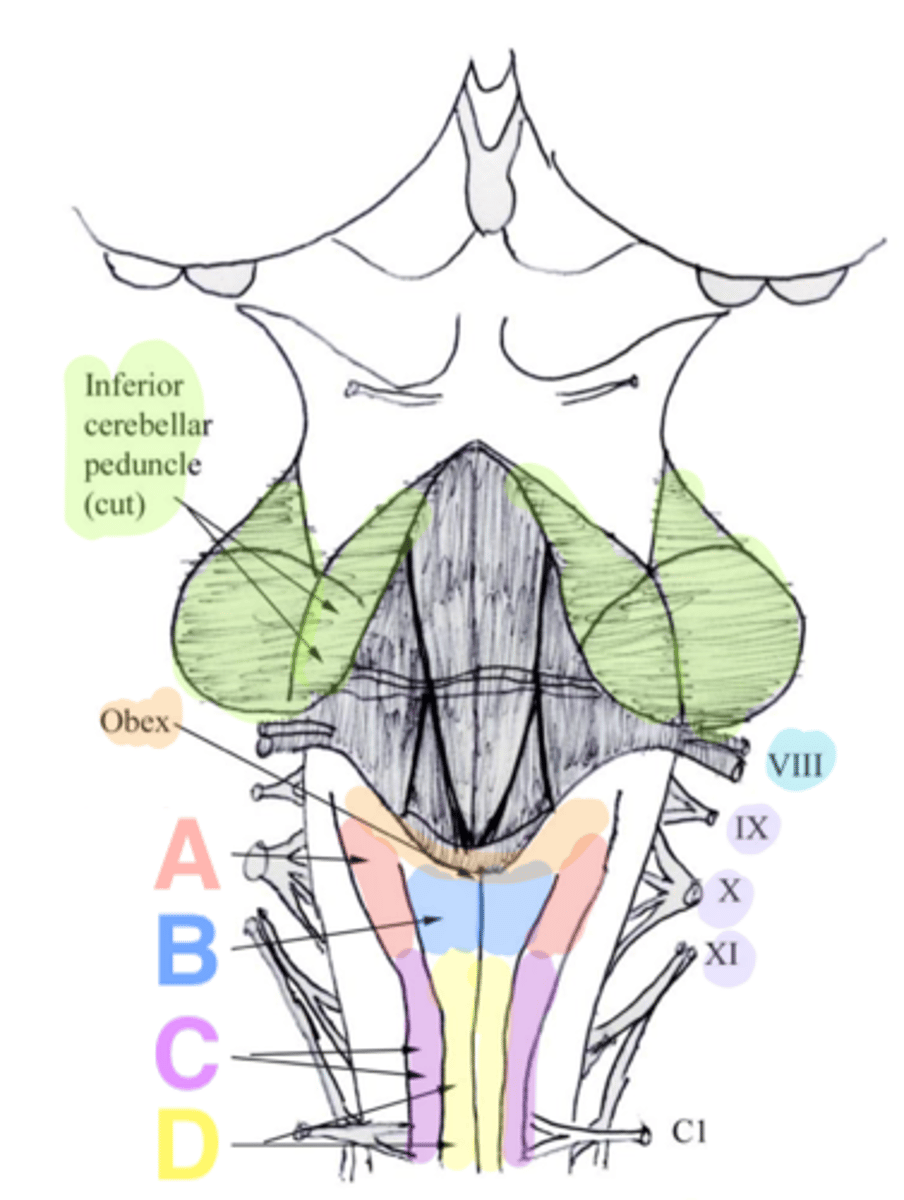

What anatomical aspect of the 4th ventricle is considered its floor?

ventral

refers to the floor of the 4th ventricle

rhomboid fossa

What forms the floor (rhomboid fossa) of the 4th ventricle?

dorsal surfaces of pons tegmentum and open medulla

inferior angle of the floor of the 4th ventricle

obex

vertical groove running in the floor of the 4th ventricle that separates it into right and left halves

dorsal median sulcus

vertical groove lateral to the dorsal median sulcus of the 4th ventricle

**same one that separated the alar and dorsal plates in the neural tube during development

sulcus limitans

refers to most of the floor of the 4th ventricle lateral to the sulcus limitans

**namesake nuclei are here

vestibular area

triangular region located in the caudal portion of the rhomboid fossa of the 4th ventricle, where the dorsal motor nucleus of CN X is

vagal trigone

Which parasympathetic nucleus is found in the vagal trigone of the 4th ventricle?

dorsal motor nucleus of X

triangular region located most medially in the caudal portion of the rhomboid fossa of the 4th ventricle, where the CN XII nucleus is

hypoglossal trigone

part of the 4th ventricle superior to the vagal and hypoglossal trigones (still medial to the sulcus limitans)

medial eminence

small bump located in the caudal portion of the medial eminence which forms from the motor fibers of CN VII as they wind around the underlying CN VI nucleus

facial colliculus

pigmented area that looks blue near the superior aspect of the sulcus limitans; cluster of noradrenergic cells

locus ceruleus

fibers that run horizontally in the central region of the rhomboid fossa of the 4th ventricle

stria medullares

area that helps to make the walls of the obex and is thought to be the "vomit trigger"

area postrema

What mostly forms the lateral walls of the 4th ventricle?

inferior cerebellar peduncles and choroid plexus

openings in the 4th ventricle that allows CSF to flow from the 4th ventricle into the pontine cistern of the subarachnoid space

foramen of von Luschka (or lateral apertures)

floor of 4th ventricle

rhomboid fossa

sulcus limitans

floor of 4th ventricle lateral to sulcus limitans

vestibular area

vasal trigone

hypoglossal trigone

medial eminence

small bump in caudal portion of medial eminence

facial colliculus

stria medullares